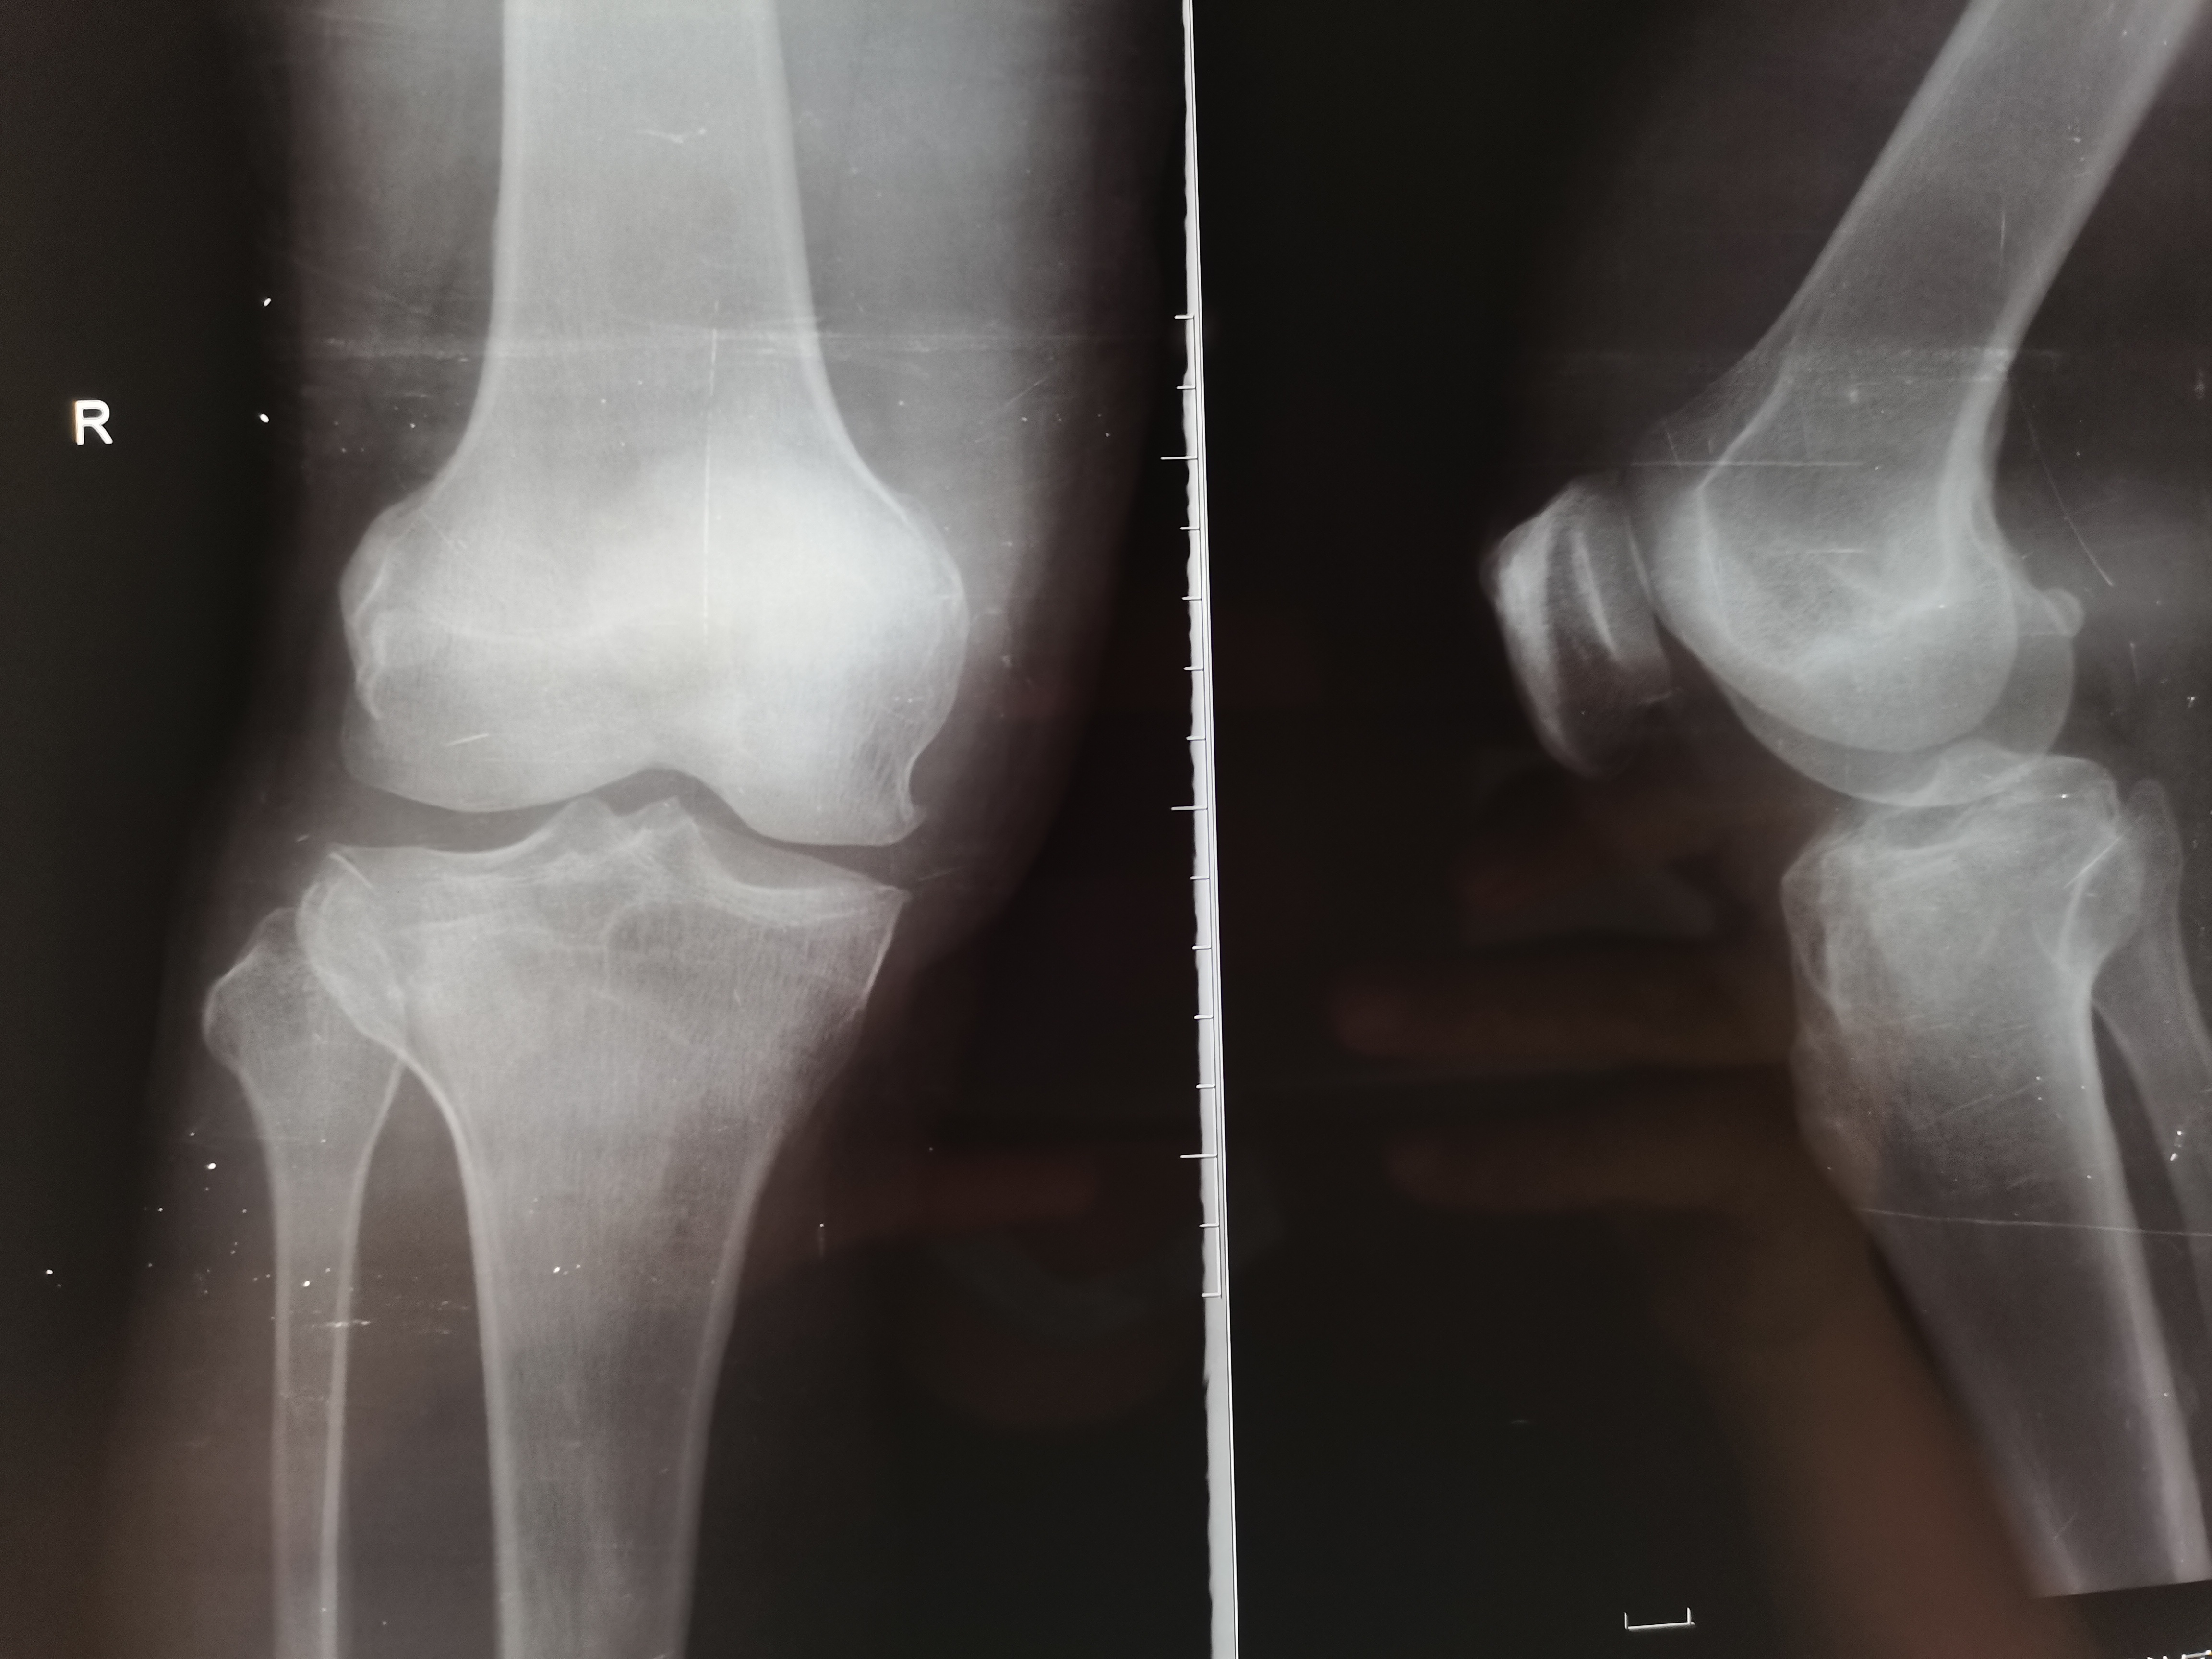

- X线片:首选初步检查,拍摄膝关节正侧位片,可明确骨折是否存在、大致移位方向,但难以显示关节面细节及软组织损伤。

- Ⅰ型:外侧平台劈裂骨折,无关节面塌陷(常见于年轻患者,高能量创伤)。

- Ⅱ型:外侧平台劈裂+塌陷骨折(最常见类型,多见于中年患者)。

- Ⅲ型:外侧平台单纯塌陷骨折(常伴软骨损伤,多见于老年人低能量跌倒)。

- Ⅳ型:内侧平台骨折(高能量创伤,易伴关节脱位、血管神经损伤,预后较差)。